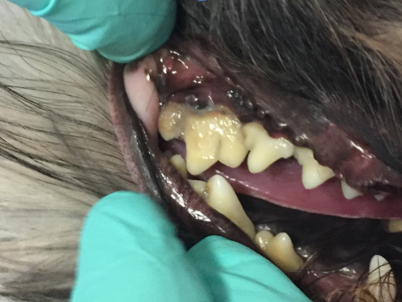

Als ich bei Leila ins Maul schaute, staunte ich schon nicht schlecht. Ich sah die Besitzerin an und fragte: „Wie alt war Leila noch mal?“ Leila war tatsächlich erst drei Jahre alt und doch wusste ich da schon, dass wir wahrscheinlich keinen Zahn retten könnten. Man sieht es wirklich nur, wenn man etwas genauer hinschaut: Leilas Zahnhälse lagen alle frei, und eitrige Beläge kamen aus der Tiefe des Zahnfachs (Abb. 2 - 5).

Solche Veränderungen treten oft bei einer hochgradigen Parodontitis auf. Eine Parodontitis ist die Entzündung des gesamten Zahnhalteapparates (also des Kieferknochens, des Zements, der Paradontalfasern und des Zahnfleischs) und wird durch die Bakterien, welche im Plaque enthalten sind, hervorgerufen. Diese zerstören die Anheftung der Gingiva am Zahn, und die Bakterien können bis zur Wurzel vordringen. Hier rufen sie Entzündungsreaktionen des Kieferknochens und der Gingiva hervor, wodurch beide sich zurückziehen und tiefe Paradontaltaschen entstehen lassen. Doch Leila hatte, wie auf den Bildern schön zu sehen ist, kaum Zahnstein oder Plaque.